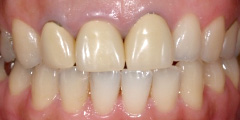

| 歯型をとり仮歯を入れました。 不自然な感じがします。 | 製作されたオールセラミック

優れた光透過性。 |

装着後 自身の歯が戻った様に自然な感じに成りました。 |